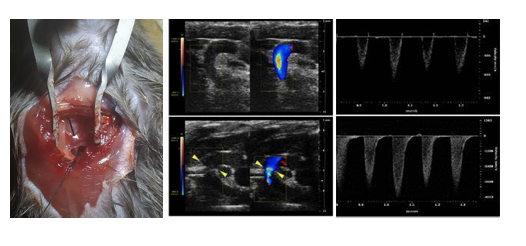

主动脉弓缩窄模型(transverse aortic constriction, TAC)最早由Rockman等于1991年正式建立,是慢性心室肥大最常用的疾病模型,用于模拟高血压或室内压增高而引起的肥厚性心肌病、心衰。TAC术后,主动脉弓部定量的缩窄引起主动脉血流受阻,左心室压力负荷增加,诱发了左心室的心室肥厚,早期以向心性肥厚为主,心功能可有效代偿,随着时间的延续,进行性发展为心腔的扩张,最终发展为心力衰竭。

根据动物品系、基因型和手术缩窄程度的不同,心室肥厚和心衰的进程不同。TAC术后1周可发展为显著性的心室肥厚,2-3周发展为心力衰竭。

案例展示: